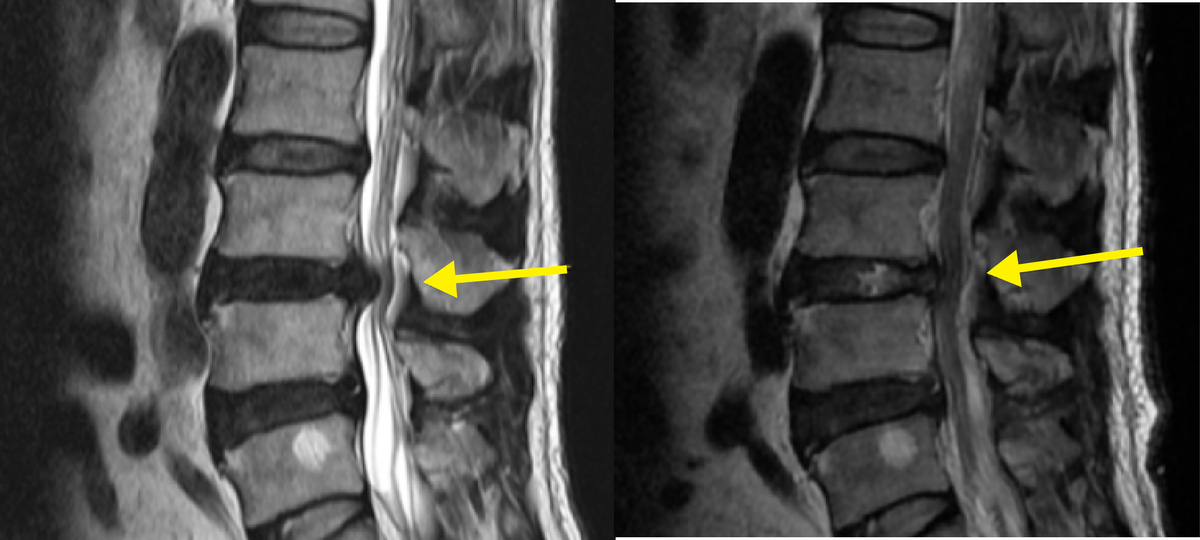

협착증은 척추관이 좁아져 신경이 눌리는 질환으로 허리를 굽히면 편하고 펴면 아픈 경향, 보행 거리 감소가 특징이다. 진단은 병력과 이학적 검사에 더해 MRI가 핵심이다. X-ray로 정렬·불안정성을 확인하고, MRI로 디스크·신경·연부조직을 정밀하게 본다.

배장호 원장은 “허리디스크는 MRI로 병소를 정확히 확인하고 약물·재활부터 신경차단술·신경성형술, 필요한 경우 최소침습 수술까지 ‘단계 치료’를 지키면 대부분 수술 없이 일상 복귀가 가능하다. 단, 다리 힘이 급격히 빠지거나 대소변 장애처럼 응급 신호가 나타나면 지체 없이 수술을 고려해야 예후를 지킬 수 있다. ”라고 강조했다.